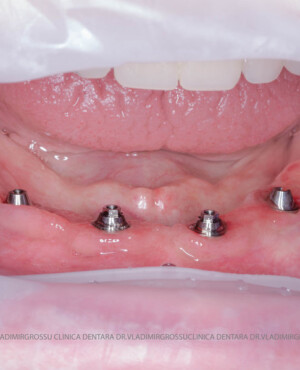

studii științifice.În cazurile de atrofie osoasă severă, când inserarea implanturilor în zonele laterale nu este posibilă fără adăugare osoasă, conceptul All-on-4 prevede plasarea implanturilor în unghiuri strategice pentru a evita zonele deficitare. Astfel, două implanturi sunt plasate în zona incisivilor laterali, iar alte două în zona premolarilor.

Această metodă este recomandată pacienților edentați total sau celor cu lipsuri dentare multiple. Procedura se realizează într-o singură etapă, iar pacientul primește proteza provizorie în ziua următoare intervenției. De regulă, proteza provizorie este realizată din masă plastică frezată. Suturile se îndepărtează după 5-7 zile.

- 4 implanturi;

- 2 multiunit-uri drepte și 2 multiunit-uri angulate, conform necesităților protetice;

- 4 abutment-uri provizorii pe multiunit-uri;

- Proteză provizorie din masă plastică frezată sau proteză mobilizabilă pregătită și ajustată la componentele protetice.